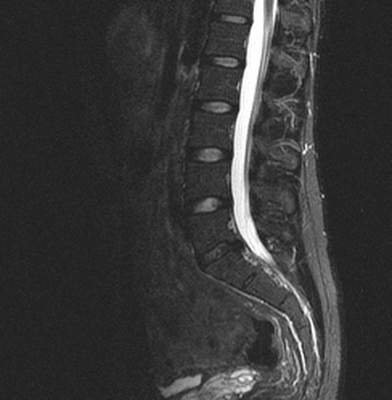

Множественные (2) гемангиомы на МРТ грудного отдела позвоночника

Результатом рентгенографии являются снимки конкретного отдела позвоночника. На них врач изучает структуру костной ткани и позвонков в целом. Увеличить детализацию снимка возможности нет. На фотографиях отдельные тени накладываются друг на друга.

При получении результатов МРТ рентгенолог имеет доступ к изображениям любого отрезка исследуемой области. Можно рассмотреть каждую связку или спинномозговой корешок, в том числе в разрезе. Цифровые технологии упрощают работу со снимками для врача. При необходимости доктор может изучить один и тот же отрезок с разных ракурсов, увеличить или уменьшить картинку.